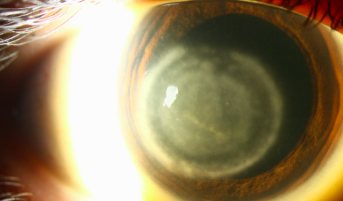

Disciform endotheliitis